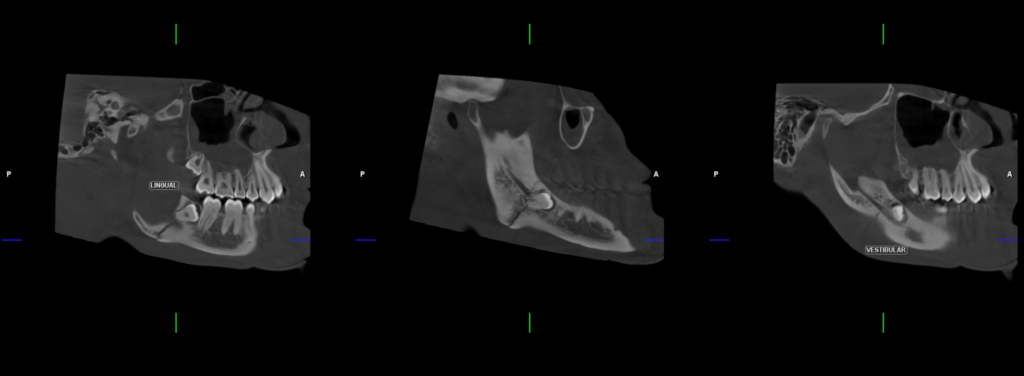

En la radiografía panorámica (Figura 1), se evidencia linea radiolucida que se extiende desde cima de reborde alveolar a nivel de zona retromolar hasta zona anterior del angulo mandibular.

Radiografia Panorámica